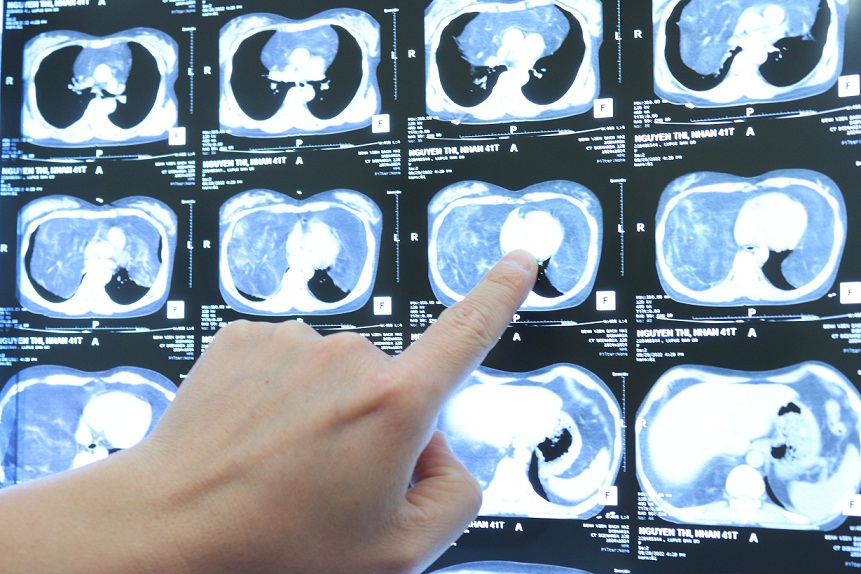

Chị Hoa bị bệnh Lupus (một loại bệnh lý gây ra do rối loạn đáp ứng miễn dịch) nhiều năm nay vẫn định kỳ đi khám và điều trị tại Bệnh viện Bạch Mai. Gần đây chị thấy đau tức ngực, khó thở nhiều, triệu chứng ngày càng nặng. Bác sỹ cho chụp cắt lớp thì phát hiện chị có u trung thất lớn, trọng lượng khoảng 4 kg, chiếm phần lớn thể tích lồng ngực. Khối u lớn làm giảm thể tích trường phổi hai bên, gây chèn ép tim và các mạch máu lớn trên nền bệnh lý mãn tính gây không ít lo ngại cho quá trình điều trị. Sau khi hội chẩn liên khoa Tim mạch, Dị ứng, Gây mê hồi sức, Phẫu thuật lồng ngực để tìm phương án, các bác sĩ đã quyết định phẫu thuật để cắt bỏ khối u.

ThS.BS. Ngô Gia Khánh, Trưởng Khoa Phẫu thuật lồng ngực mạch máu – Bệnh viện Bạch Mai, người trực tiếp phẫu thuật cho bệnh nhân Hoa cho biết: Khối u là tổ chức mỡ, chiếm toàn bộ trung thất và phần dưới khoang màng phổi, ranh giới u tương đối rõ với các tổ chức xung quanh. Với trọng lượng sau khi cắt khoảng 4kg, khối u khổng lồ khiến hai phổi của bệnh nhân bị đẩy lên trên, ôm quanh tim và các mạch máu lớn. Đây chính là nguyên nhân dẫn đến việc bệnh nhân Hoa bị tức ngực, khó thở. Chia sẻ về độ phức tạp của ca phẫu thuật, ThS.BS. Gia Khánh cho biết: Khối u to, đường mổ lớn nên nguy cơ mất máu, đau sau mổ rất lớn. E kip gây mê và phẫu thuật đã phải phối hợp và theo dõi sát từng chỉ số huyết động trong mổ, phẫu tích, bảo tồn các cấu trúc mạch máu, thần kinh trong toàn bộ cuộc mổ để hạn chế mất máu mà vẫn lấy trọn khối u lớn, giải phóng hai phổi khỏi bị chèn ép.

BS Khánh và BS Minh xem phim chụp cho bệnh nhân

Hình ảnh khối u khổng lồ trong khoang ngực